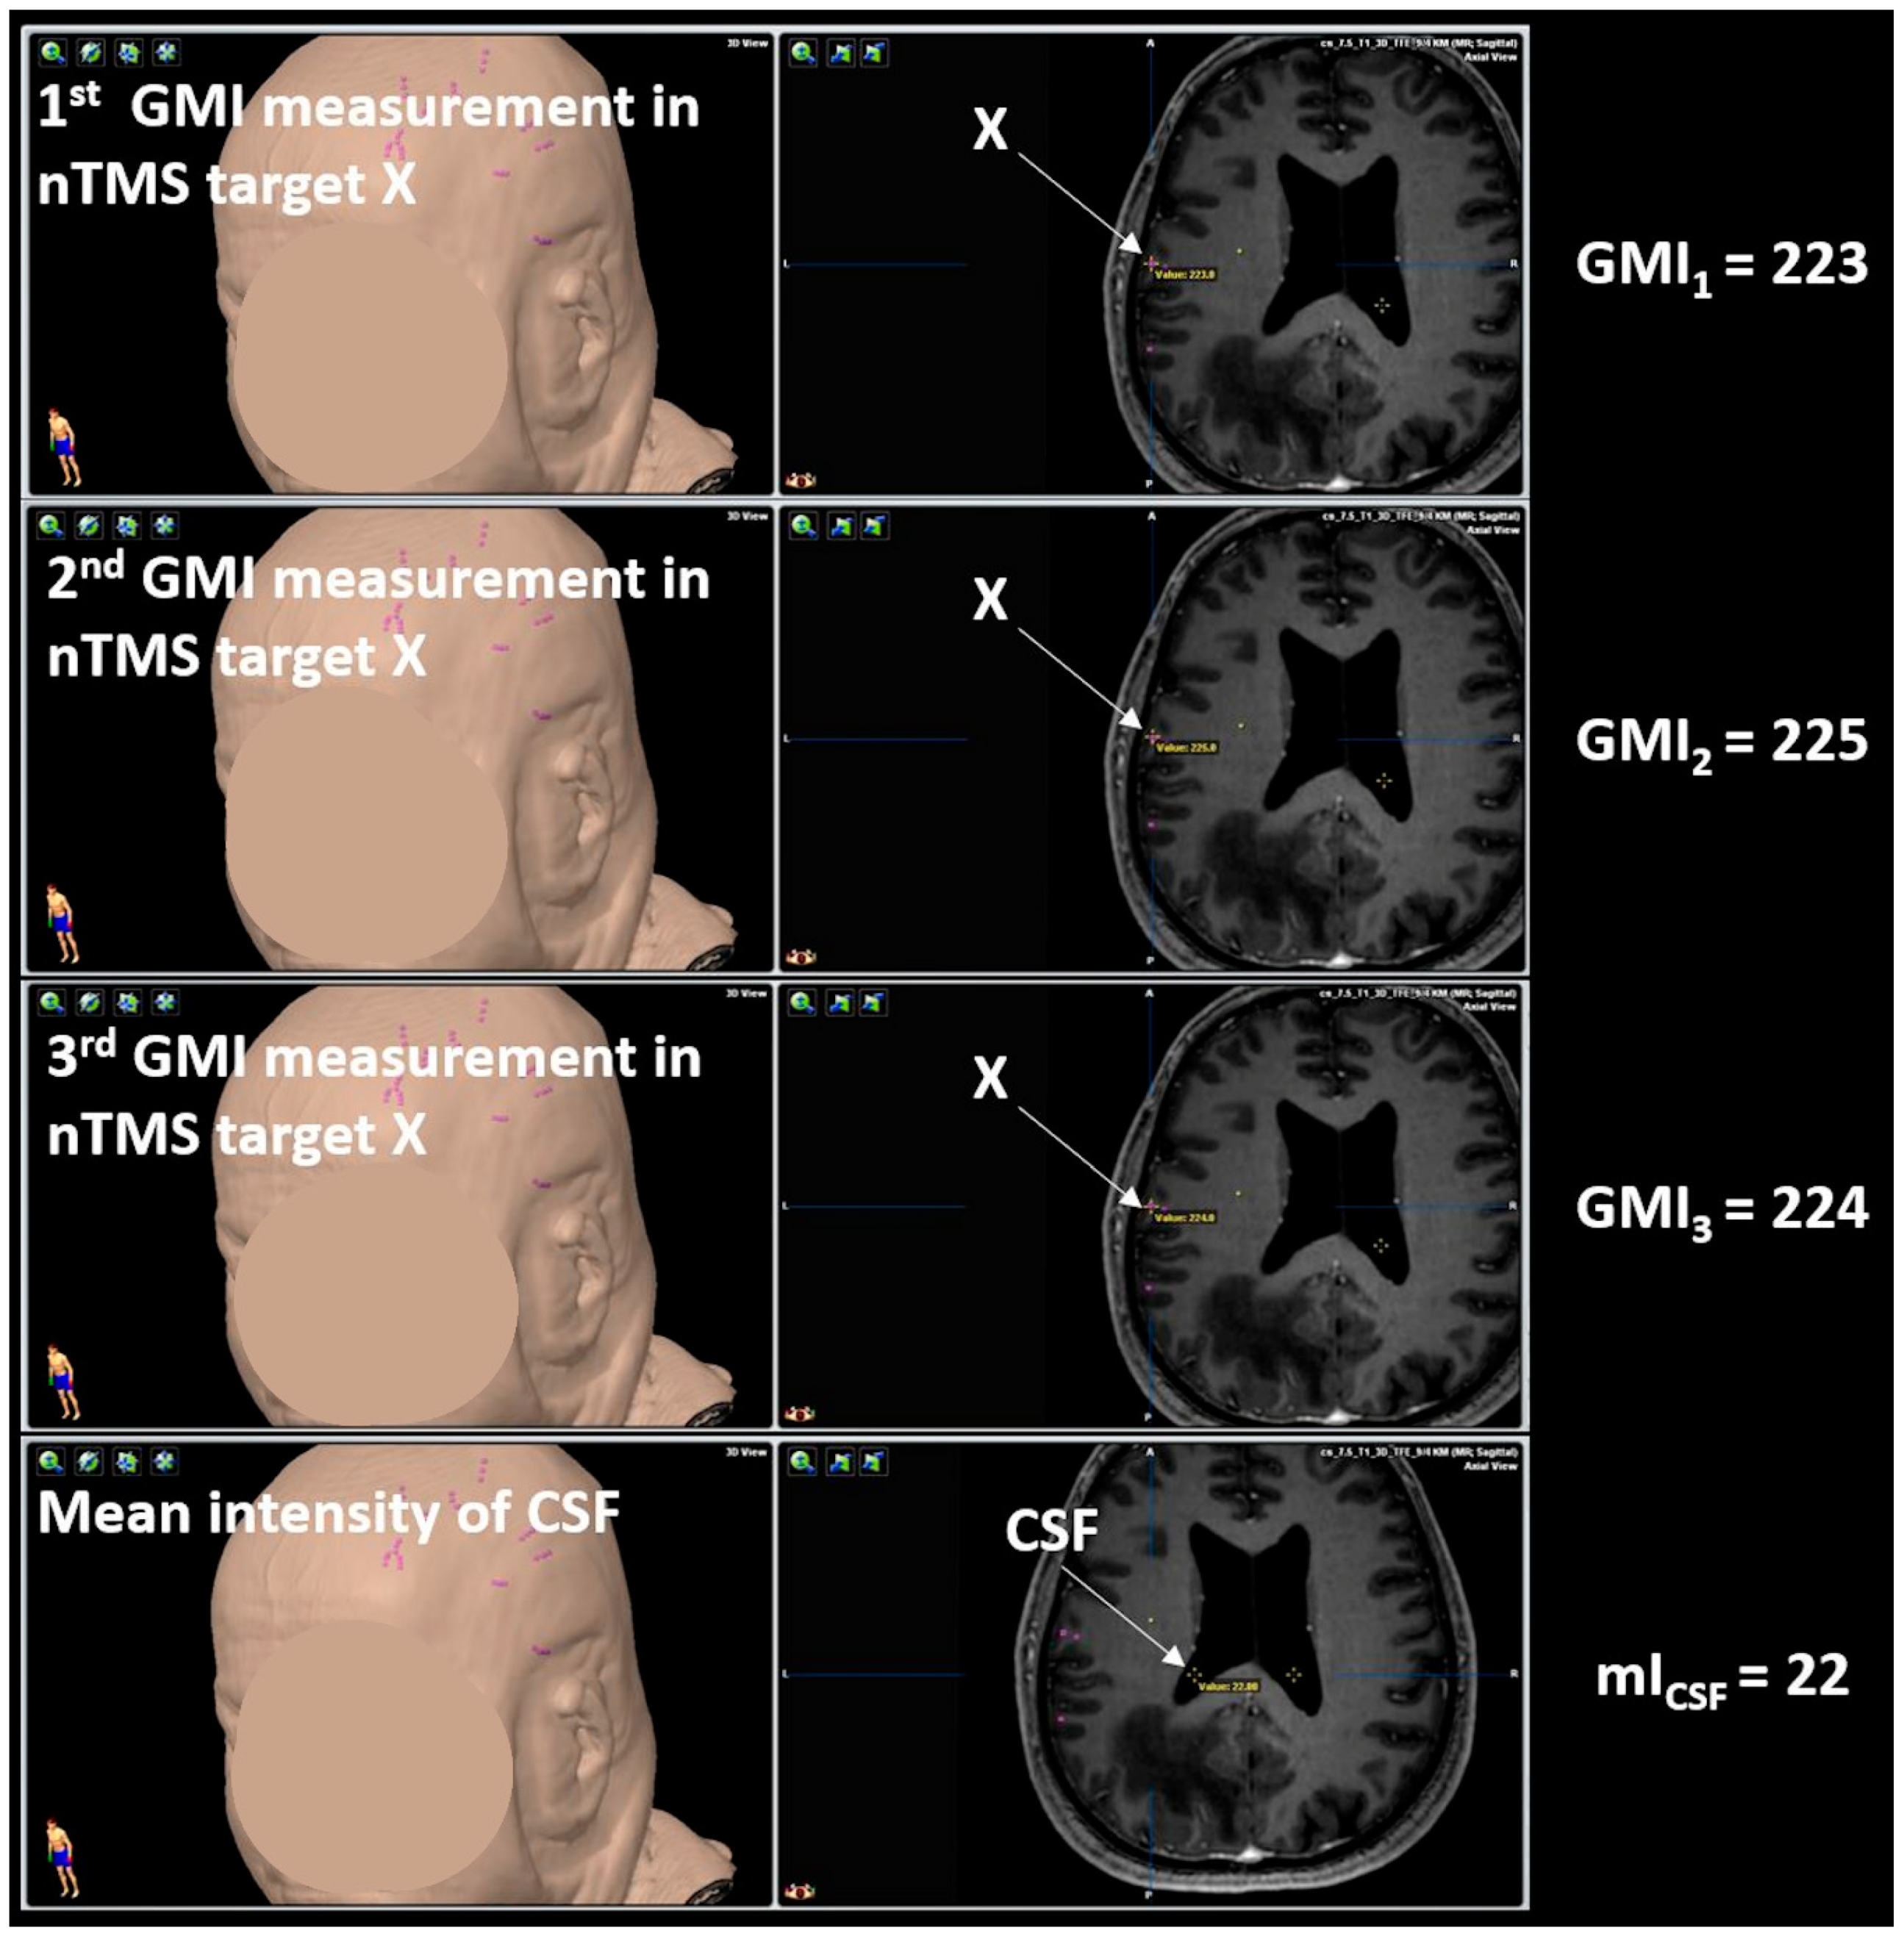

2.7.1. Gray Matter Intensity

4.1. Gray Matter Intensity